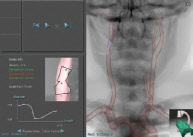

PROcedure Rehearsal Studio’s real-time CT images correspond to active fluoroscopic views to help you understand your patient’s anatomy and to assist in effective CT interpretation and study.

PROcedure Rehearsal Studio automatically identifies structures, segments relevant vasculature from surrounding structures, and features all the standard functionality of vascular imaging and analysis workstations, including vessel views and cross-sections.

This unique feature automatically identifies and quantifies vessel stenosis and then displays its location, severity and dimensions.